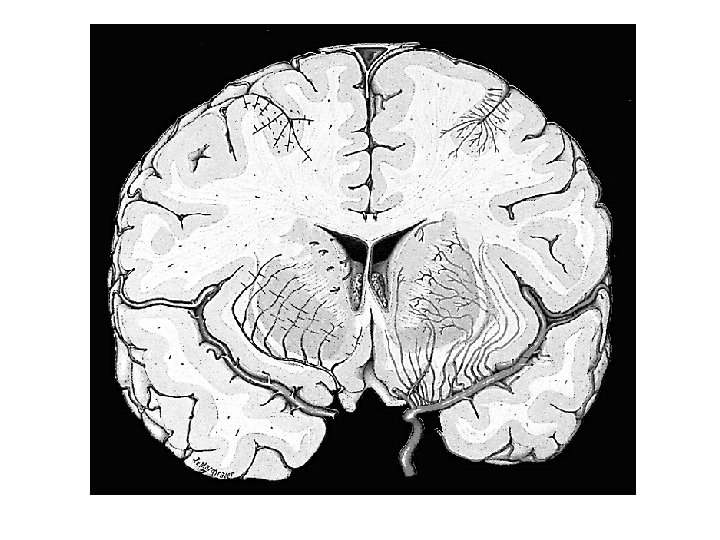

X 120 Anterior Comm ACA Fornix IIIrd Ventricle Thalamus & Pulvinar MCA Corpus Callosum Lateral Ventricle (Atrium) Optic Radiations Primary Visual Cortex Caudate Nuc (2 X) Internal Cap (AL, Genu, PL) Putamen Globus Pallidus (Ext & Int) External & Extreme Cap Claustrum Insular Cortex PCA